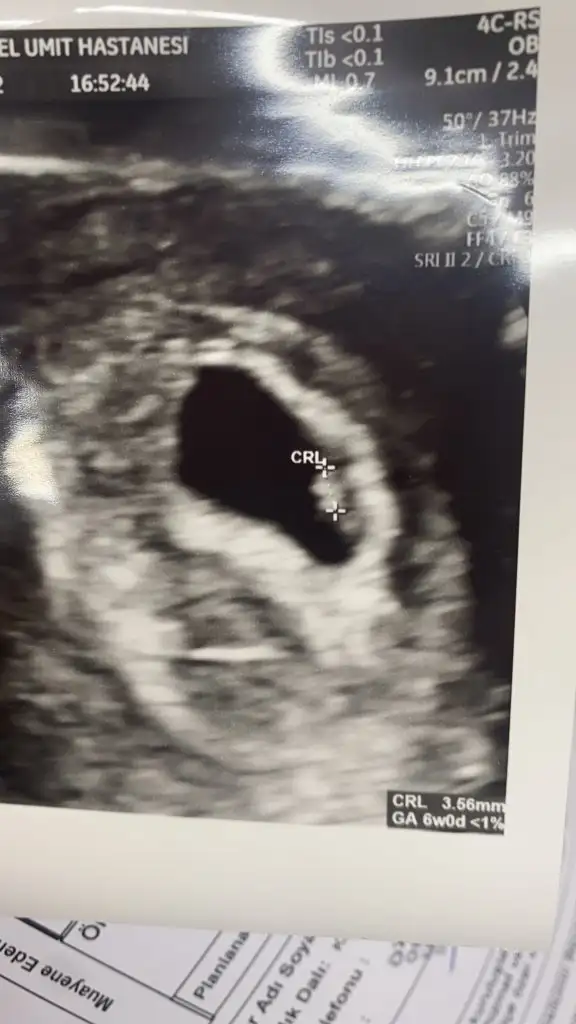

5 ve 14. haftaya kadar olan ultrason fotolarınızı paylaşın. Vajinadan mı yoksa karından mı çekildiğini ve kaç haftalık olduğunu da mutlaka belirtin.:anneadayı: